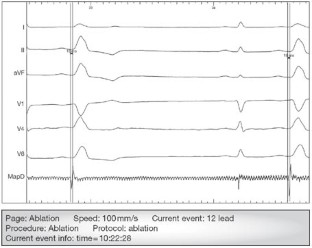

Background A 44-year-old female presented with a long history of chest pain, palpitations and increasing dyspnea. Electrocardiography and 24 h Holter monitoring revealed multiple premature ventricular complexes (PVCs), and echocardiography demonstrated significant left ventricular dilatation and systolic impairment. After further investigation it was concluded that this cardiomyopathy was secondary to the observed multiple PVCs and that these represented a potential target for treatment.

Investigations Electrocardiography, echocardiography, cardiac MRI, 24 h Holter monitoring, coronary angiography, tilt testing and invasive electrophysiological testing using a multielectrode array catheter.

Management Electrophysiological mapping and cryoablation of the focus of the ventricular ectopy.